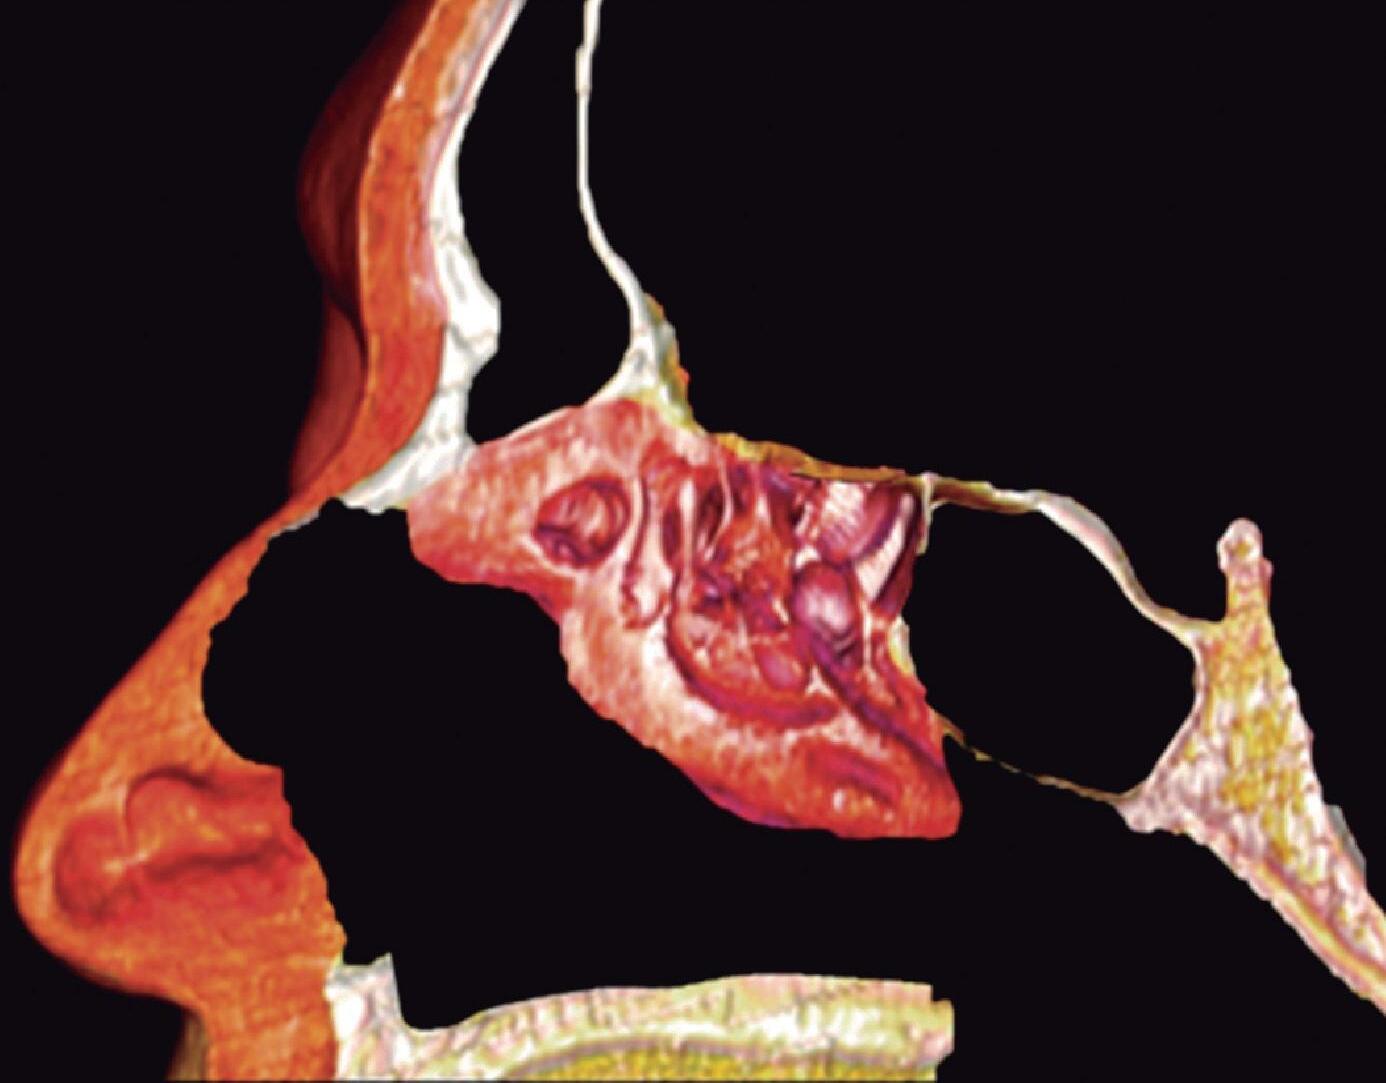

1-4. TC e reconstrução 3D com destaque para estrutura etmoidal (em vermelho), funcionando como câmaras de baixa pressão para drenagem do seio maxilar.

1-7. TC com reconstrução 3D mostrando em vermelho apenas o seio etmoidal e não o osso etmoidal, e sua relação com a fossa nasal, o seio maxilar, órbita e fossa anterior.

1-8. Osso etmoidal e seio etmoidal (amarelo) observar o aspecto incompleto do teto do seio etmoidal que será coberto pelo osso frontal (rosa).